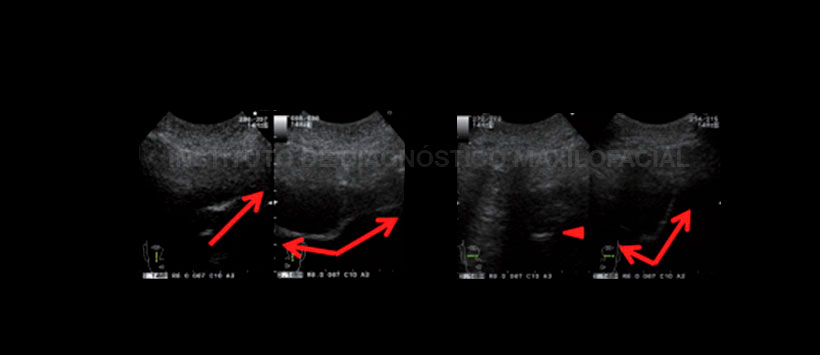

Por otro lado, el uso del ultrasonido Doppler color en el caso de infección sinusal ha sido sugerido para el diagnóstico de sinusitis maxilar. En base a estudios previos, se puede concluir que la corriente de sonido puede producirse en las secreciones sinupresoras del seno, pero no en las secreciones mucosas purulentas debido a su alta viscosidad. A diferencia de la sinusitis no purulenta en la sinusitis purulenta, el ultrasonido Doppler a color también muestra un aumento en el flujo sanguíneo. En consecuencia, las secreciones purulentas son distinguibles de las secreciones serosas sinusales.

La sinusitis es un proceso inflamatorio y la inflamación se ha asociado con un aumento del flujo sanguíneo. Por lo tanto, se puede formular la hipótesis de que en el momento de la sinusitis, las arterias que transportan sangre a los senos paranasales aumentan la velocidad y el diámetro del flujo sanguíneo para aumentar el flujo sanguíneo a los senos paranasales.

Los hallazgos en el estudio de Islam M, et al. (2018) demostraron que la ecografía convencional tiene una gran concordancia con la TC como el estándar de oro en el diagnóstico de la sinusitis maxilar pediátrica. Si se agrega el Doppler color y se consideran los hallazgos específicos presentados en este estudio (signos de Ghasemi), se mejorará el valor diagnóstico de esta modalidad.

Figura 3: Ultrasonografía. Dirección vertical y horizontal de inspección